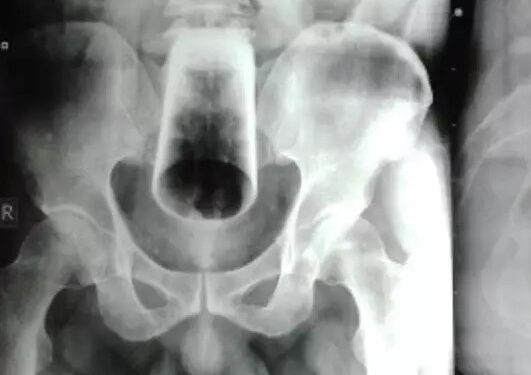

Homem passa por cirurgia após ficar 3 dias com copo preso no ânus

Reprodução/ Foto: Journal of Nepal Medical

Um homem, de 47 anos, passou por uma cirurgia após ficar três dias com um copo de vidro preso no ânus.

O homem chegou no pronto-socorro do Hospital de Ensino da Faculdade de Medicina do Nepal negando a inserção proposital. Entretanto posteriormente admitiu usar o copo “para fins de autogratificação quando estava embriagado”.

O homem disse que tentou remover o copo sozinho mas não conseguiu, e que já estava há 3 dias com o copo no ânus. Ele passou por uma cirurgia com uma incisão feita no intestino.

Ele segue se recuperando.